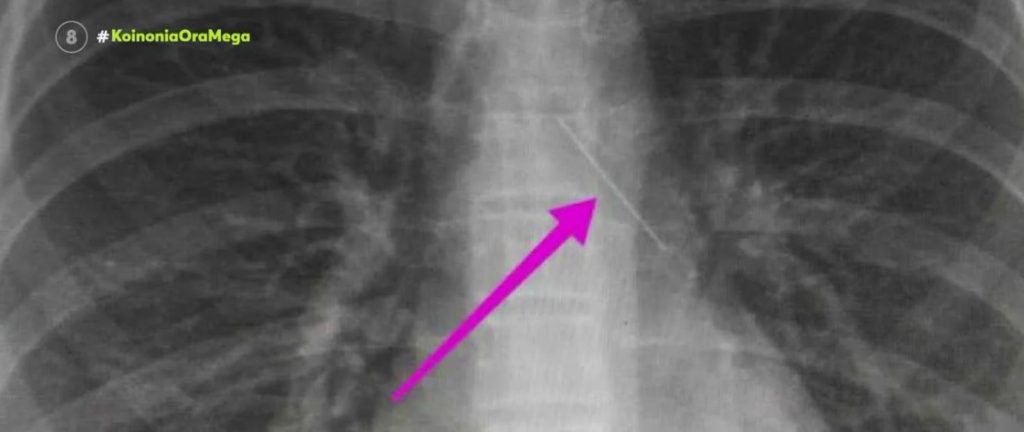

View more ΑΝΗΛΙΚΗ Θεσσαλονίκη: Ανήλικη κατάπιε καρφίτσα – Μάχη των γιατρών για να την βγάλουν από τα πνευμόνια της